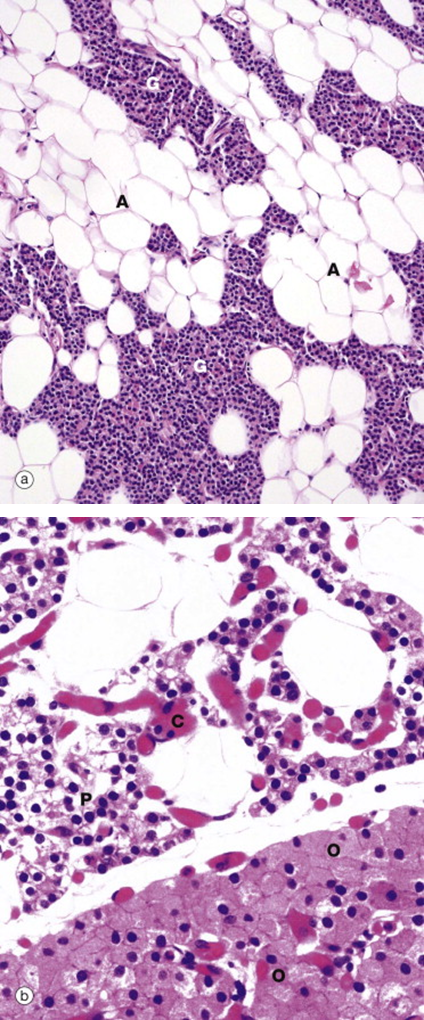

Where are these tissue samples taken from?

Parathyroid. Recognize from the presence of adipocytes.

Identify the portions of this tissue. What is this gland?

Adrenal Gland

Identify the layers of the Adrenal gland shown.

•Capsule (Cap)

•Cortex

–Three zones:

•Zona glomerulosa (G)

•Zona fasciculata (F)

•Zona reticularis (R)

•Medulla (M)

Where is this from? What layers are shown?

Z. Reticularis

Medulla